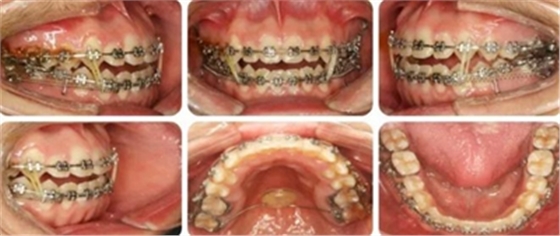

治療過程

6個(gè)月,上牙列擁擠得到解除。上下頜植入種植釘,用于上后牙壓低及下牙列遠(yuǎn)移。

14個(gè)月,前牙開頜得到改善,配合使用垂直牽引。